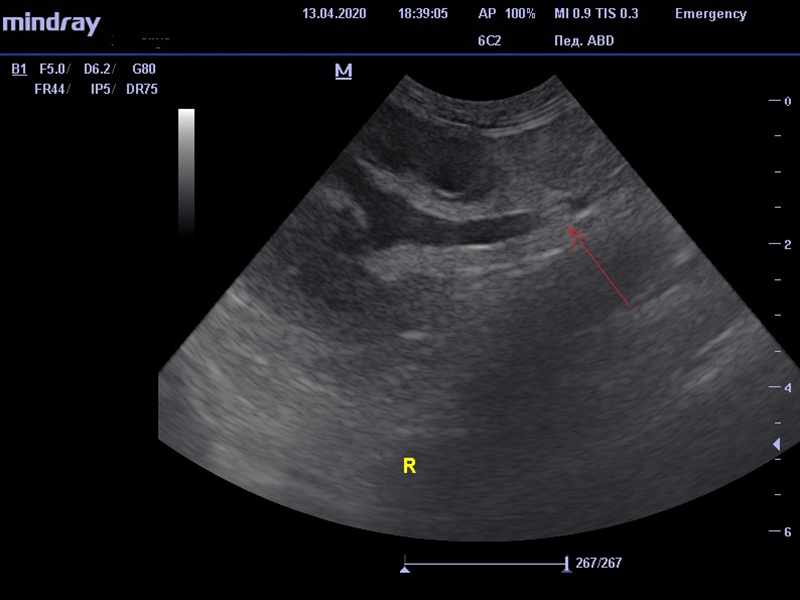

В качестве диагностики врачом было проведено ультразвуковое исследование, в результате чего было выявлено утолщение стенки мочевого пузыря, наличие осадка в мочевом пузыре. При исследовании почек отмечено повышение эхогенности мозгового слоя, а также наличие односторонней пиелоэктазии – патологического расширение лоханки почки. Мочеточник также был расширен, в его проксимальной части визуализировалась эхогенная структура, не дающая акустической тени, далее мочеточник сужался. Предполагалось, что данная структура в мочеточнике является сгустком слизи, которая может образоваться в силу бактериальной инфекции мочевыделительной системы.